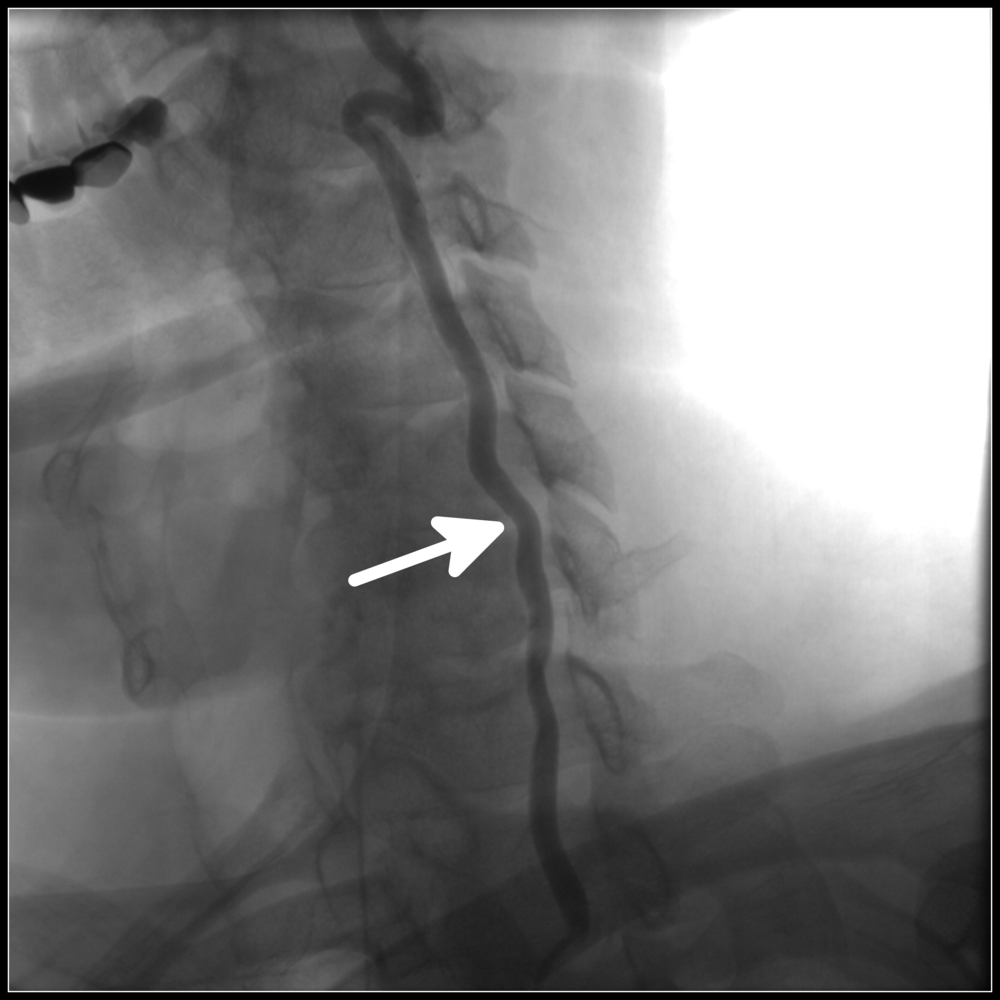

- ангиография – выполняется при необходимости уточнения данных предыдущих исследований, проводится для планирования лечения при присутствии тромбов.